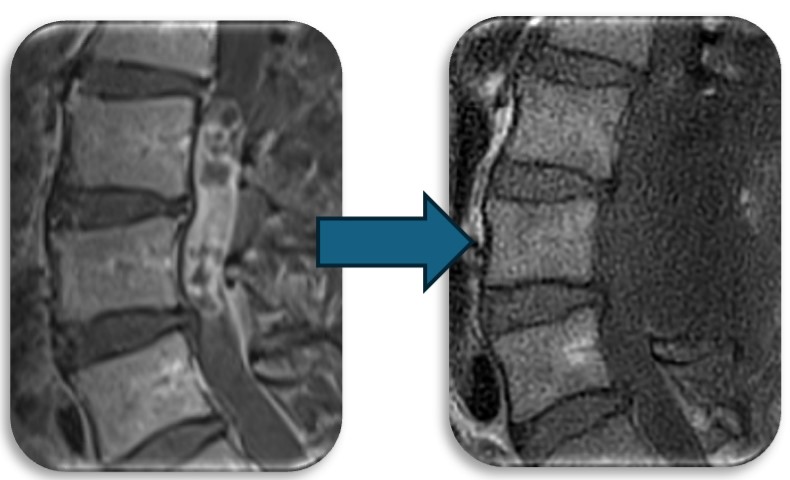

(代表例①)

頚部の脊柱管狭窄症に対して、首の後ろから手術する椎弓形成術を行なった症例です。脊柱管と呼ばれる脊髄が通るトンネルの屋根部分にあたる椎弓を縦割し観音開きで広げ、さらに新しい屋根の代わりとなる金属プレートを被せることによって脊柱管を広げます。